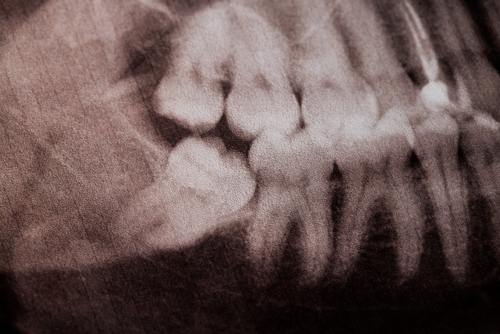

Dental extraction becomes necessary when decay, trauma, or infection has compromised the tooth beyond repair. Our clinical process includes digital imaging, surgical assessment, and evaluation of whether preservation through root canal therapy is possible. If extraction is indicated, we use minimally invasive techniques to ensure predictable, efficient results.

Your visit begins with a detailed clinical evaluation, including digital X-rays or CBCT imaging to assess tooth structure, root anatomy, and surrounding bone. Dr. Kerikorian explains your treatment options clearly and recommends the approach that offers the best long-term outcome. If an dental extraction is needed, the procedure is performed with a minimally invasive technique and careful attention to comfort. Our team also reviews post-procedure guidance and next-step restorative options, such as implants, when appropriate.

Green California Dental Group uses modern surgical instruments, digital radiography, and 3D imaging to plan dental extractions with greater accuracy and safety. Nitrous oxide is available for patients who prefer additional comfort, and sedation can be provided for more complex surgical cases. This combination of technology and clinical precision allows us to deliver efficient treatment with reduced stress, minimal discomfort, and predictable healing.